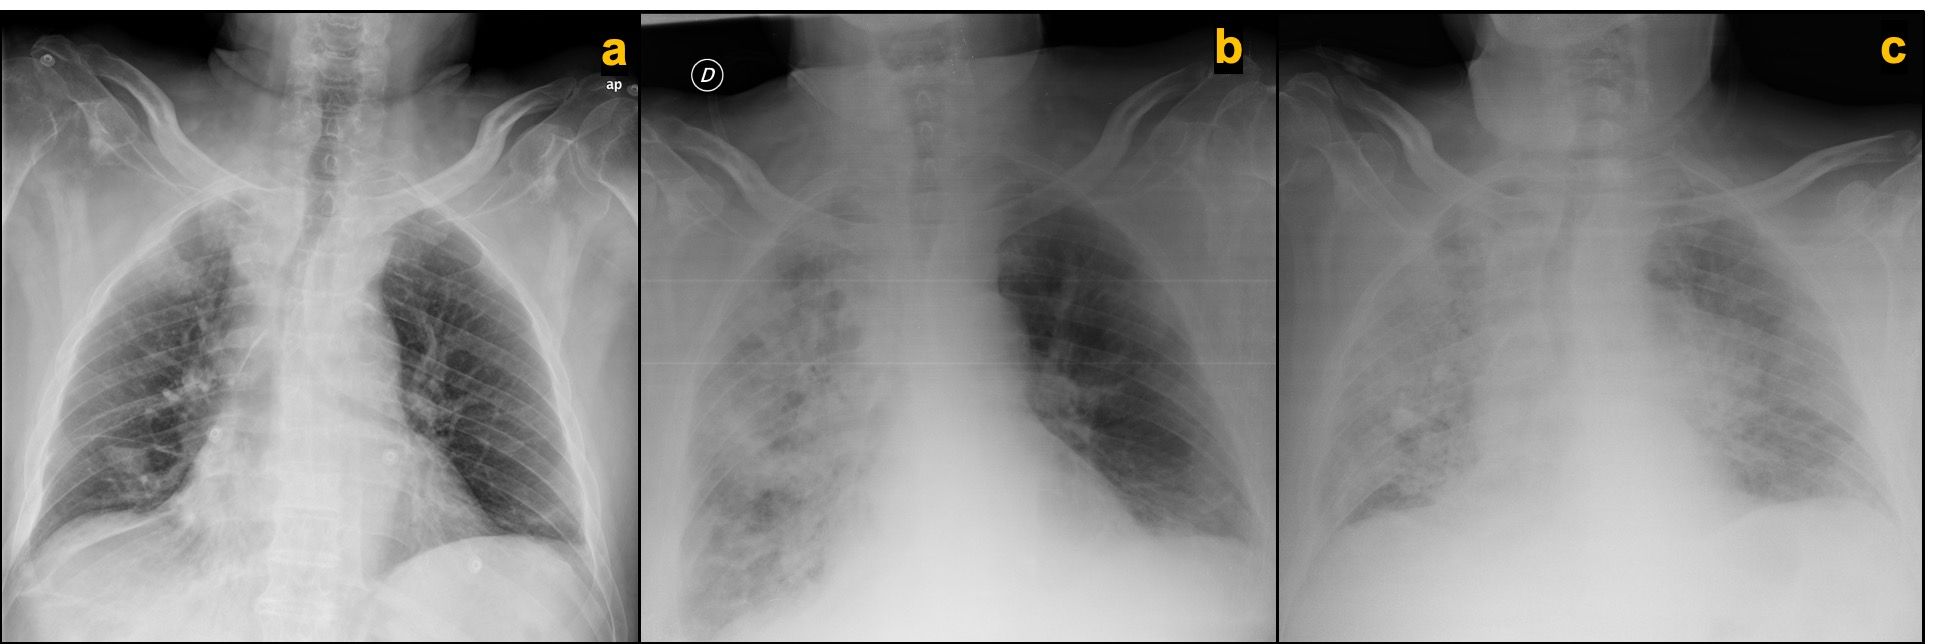

Four days into this hospitalization, the patient developed respiratory symptoms characterized by shortness of breath and cough. Pulse oximeter confirmed by blood gas analysis revealed hypoxemia, requiring supplemental oxygen via nasal cannula at 2 L/min to maintain an oxygen saturation level of more than 90%. A chest x-ray compared with the prior one taken a month ago showed bilateral patchy opacities predominantly on the right lung (Figures 1A and B). Nasopharyngeal swab specimens were positive for severe acute respiratory syndrome coronavirus 2 (SARS-CoV-2) by real-time reverse transcriptase-polymerase chain reaction (rRT-PCR).

Figure 1. Chest x-ray comparison of normal study 1 month prior to admission, (A) at time of respiratory symptoms initiation showing bilateral patchy infiltrates with right lung predominant distribution, (B) and 48 hours after treatment initiation at time of symptoms aggravation consistent with progression of bilateral lung infiltrates (C).

Treatment with antibiotics with aztreonam, ciprofloxacin, and linezolid (because of his β-lactam allergy); antiretroviral therapy with lopinavir-ritonavir; and low-molecular-weight heparin (LMWH) thromboprophylaxis was started. After 48 hours of full medical therapy, his clinical condition deteriorated and his oxygen requirements increased. A follow-up chest x-ray revealed worsening bilateral patchy infiltrates (Figure 1C). A multidisciplinary discussion among the internal medicine, pulmonology, intensive care, and medical oncology teams was held. The patient was not considered a candidate for mechanical ventilation due to a shortage of intensive care unit beds as a result of the pandemic, neoplastic disease in progression with second-line therapy, poor performance status, and coexisting comorbidities. He was sent home with palliative care with quarantine precautions for himself and his family, and died 3 days later due to respiratory failure.